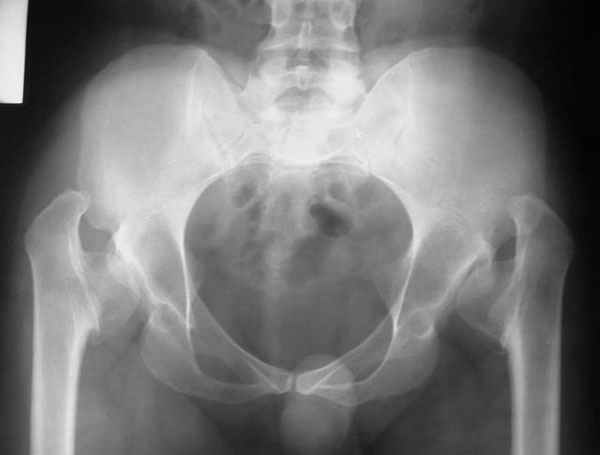

It appears that this patient has bilateral congenital hip displasia, as presented on the radiographs. As shown, the problem involves both sides of the hip joint: the acetabulum and proximal femur.

This patient is noted to have a very vertical joint surface orientation, as well, with retroversion of the acetabulum.

In a hip with normal version, (on discussion list) Hip Pain (Dr.Kullerkann) the lines connecting the anterior and posterior acetabular wall as seen on an AP radiograph usually intersect at one point near the superior and lateral portion of the acetabulum. As an example of an abnormal hip, a patient with a retroverted acetabulum will show the figure 8 pattern, with the two shadows crossing over the femoral head. In this particular patient, again it appears that there is a significant amount of retroversion of the acetabular wall, as the anterior wall appears to be more anteriorly displaced than in a normal hip.

The pre-operative planning would need to be done with the use of more radiographs for assessment of the hip dysplasia. These x-rays include a repeat AP pelvis, separate AP and lateral of the hips, long-standing femoral axis views of both legs, false profile view, as well as abduction and adduction films.

Pic. 1-5 preop plan; 6-8 similar case